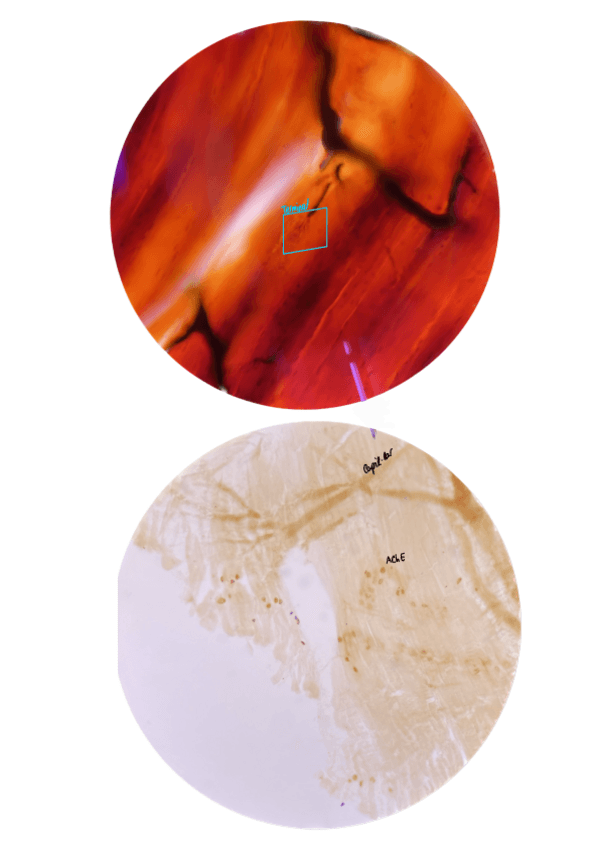

PRÀCTIQUES LABORATORI

He publicado nuevos apuntes de 2º Histología del Sistema Nervioso: PRÀCTIQUES LABORATORI

PRACTICA-1.pdf

PRACTICA-2.pdf

PRACTIQUES-UNIDES.pdf

He publicado nuevos practicas de 2º Histología del Sistema Nervioso: Histo-SN-PRACTIQUES-2024-2025.pdf

He publicado nuevos apuntes de 2º Histología del Sistema Nervioso: Practiques-histologia-del-sistema-nervios.pdf

He publicado nuevos practicas de 2º Histología del Sistema Nervioso: Ejemplo-guion-resuelto-practicas-histo-SN.pdf